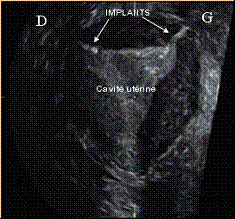

Une échographie tridimensionnelle (3D) de l’utérus et des trompes, réalisée trois mois après l’intervention, permet de s’assurer que le positionnement des implants est adéquat et que la patiente peut cesser toute autre méthode contraceptive utilisée (Figure 3).

(Figure 3)